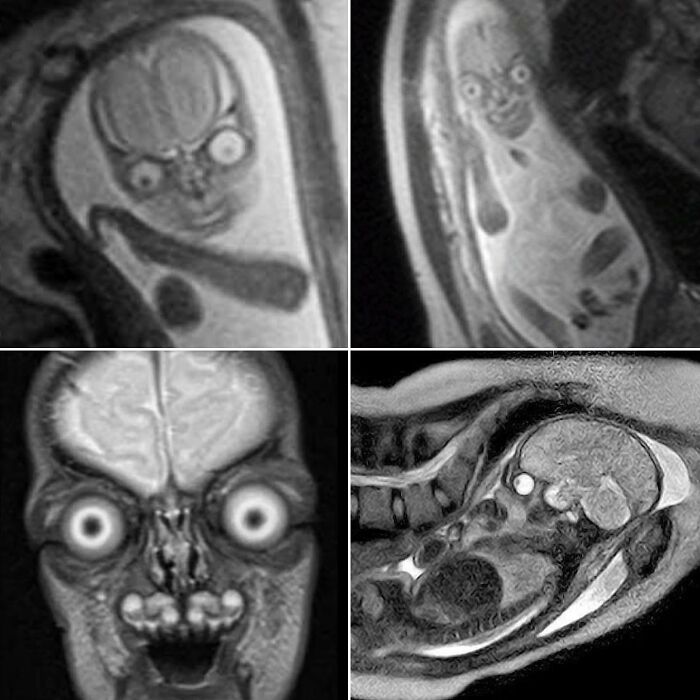

Genuine MRI Scans Of Human Babies In The Womb

Possessing menacing eyes and devilish grins, you would be forgiven for assuming these were just aliens from a Hollywood sci-fi blockbuster.

These images were circulating on social media apps and while some suggest they have been traumatised by viewing such discomforting images, others seem to find them comical.

Some users even believed the fetus was an extra-terrestrial being.

Yet, believe it or not, they are not fake.

Instead, they are genuine MRI scans of human babies in the womb.

MRI scans are different to ultrasounds. Parents are not regularly offered MRI throughout their pregnancy and will typically only have the scan if there is a concern for the child's growth and development.

For example, they can help define and detect neck, thoracic, abdominal and spinal malformations in fetuses.

When used during pregnancy, however, MRIs can produce a very life-like image of their baby.

The detailed black and white images burst the bubble of many parents who blindly believe their tiny tot is going to be adorable through and through.

One user said MRIs are discouraged during pregnancy because 'people would realise they're incubating nightmare demons and would be rightfully terrified'.

We can confirm these images are authentic and real.

MRI uses magnetic fields and radio waves to produce detailed images of the inside of the body.

The eyes and brain have high levels of 'signal' — a radio wave — which causes them to appear brighter and stand out on the scan.

Other parts of the body give off lower levels, and therefore appear darker.